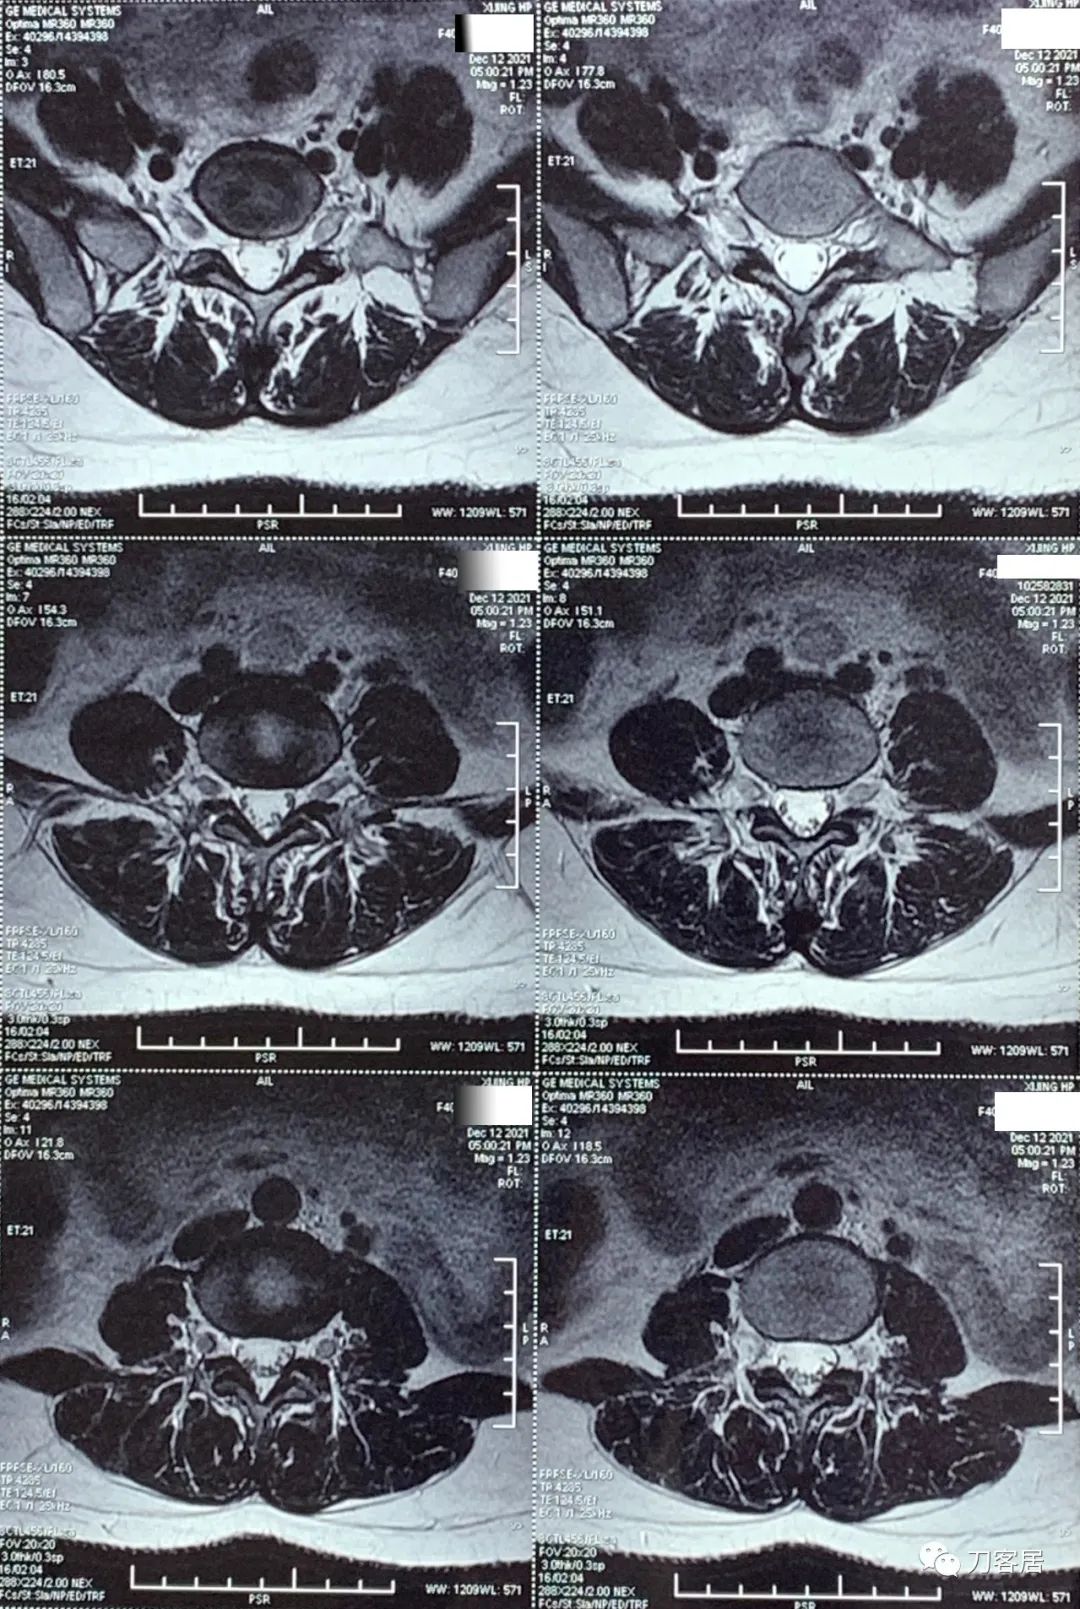

自带腰椎MRI检查未见异常。腰椎X线片提示左侧腰5横突肥大。自带外院骨密度检查结果正常。

20211212西京医院腰椎MRI.